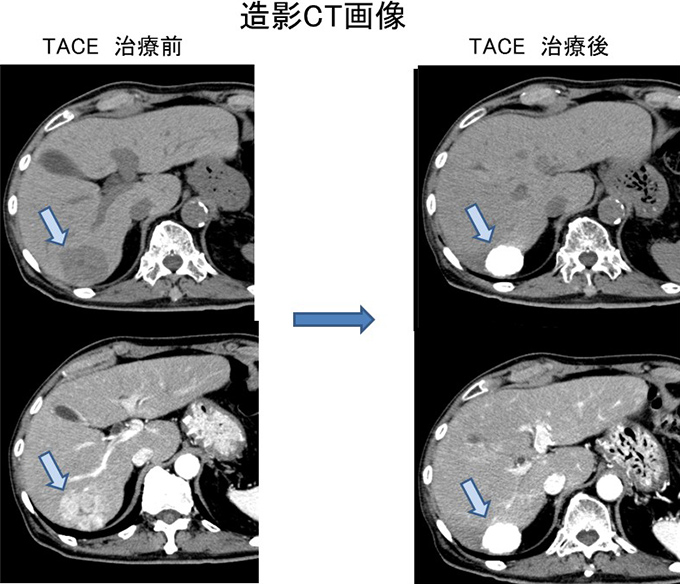

治療効果は通常造影CT等を用いて行います。治療前の造影CTで認めた早期増強域に一致して治療後のCT画像ではリピオドールの集積による著明な高吸収域を認めます(図3)。

TACE 治療前とTACE 治療後の造影CT画像

図3 治療前後の造影CT画像